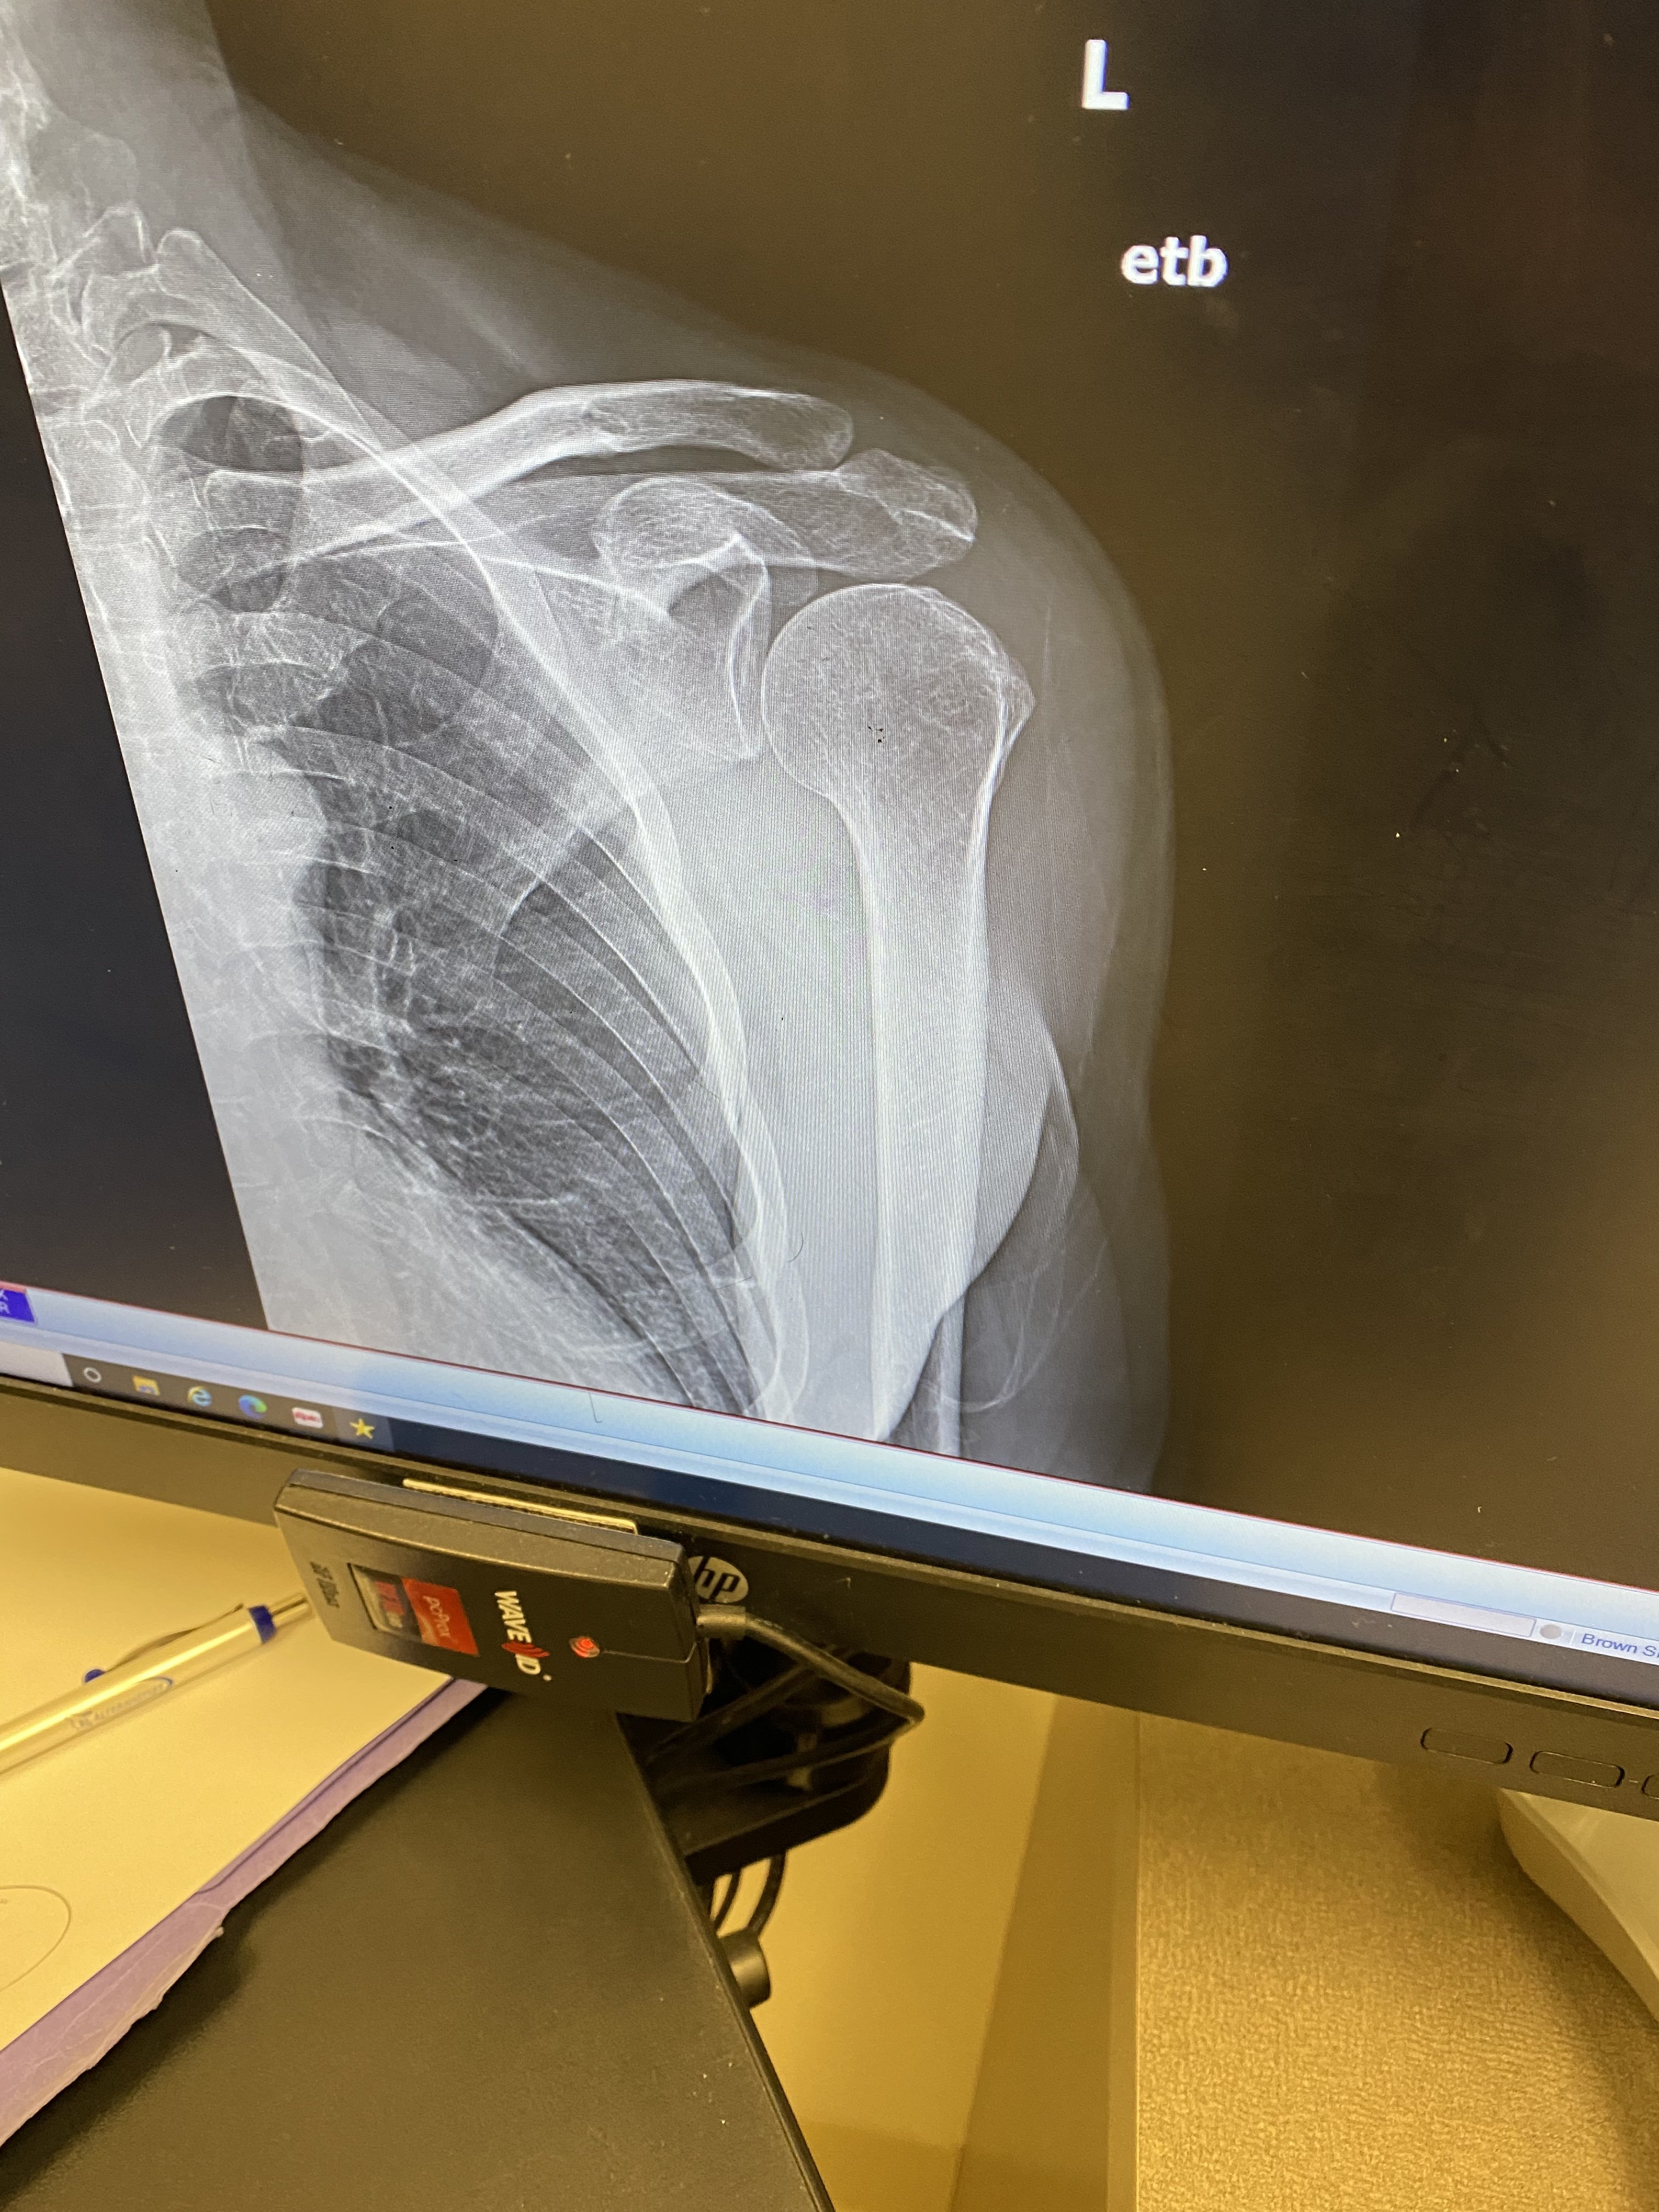

More X-Rays were taken today to confirm proper hardware alignment and this time I took screenshots of the computer when I was shown the pictures of my shoulder.

The first picture is before the surgery showing how the ball at the top of my upper arm bone is no longer in contact with the cup, that is because my Rotator Cuff Tendon has completely torn away.

What it doesn’t show is the extensive arthritis that had started to destroy the ball where it should have been in the cup.